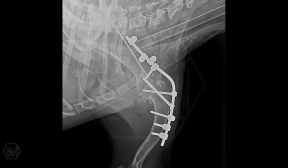

In our case, we created a shoulder arthrodesis on an 11-year-old 16kg female beagle dog with a 2.7 SOP-LC system and 4-4 clamps. The dog developed chronic arthritis and arthrosis, the biopsy did not confirm a tumor, only chronic inflammation.

There is no weak point in bridging the joint, which is inevitable in a plate bridging. Another great advantage is that the clamps can be placed according to anatomical needs, on either side of the rod and the screws can be inserted in any direction. Maximum stability is provided by the locking clamps, which is especially advantageous in a thin bone (scapula) or a bone with a porotic or thinned cortex (leg that has been used less for a long time). We have used the system several times in reoperations due to a broken plate.